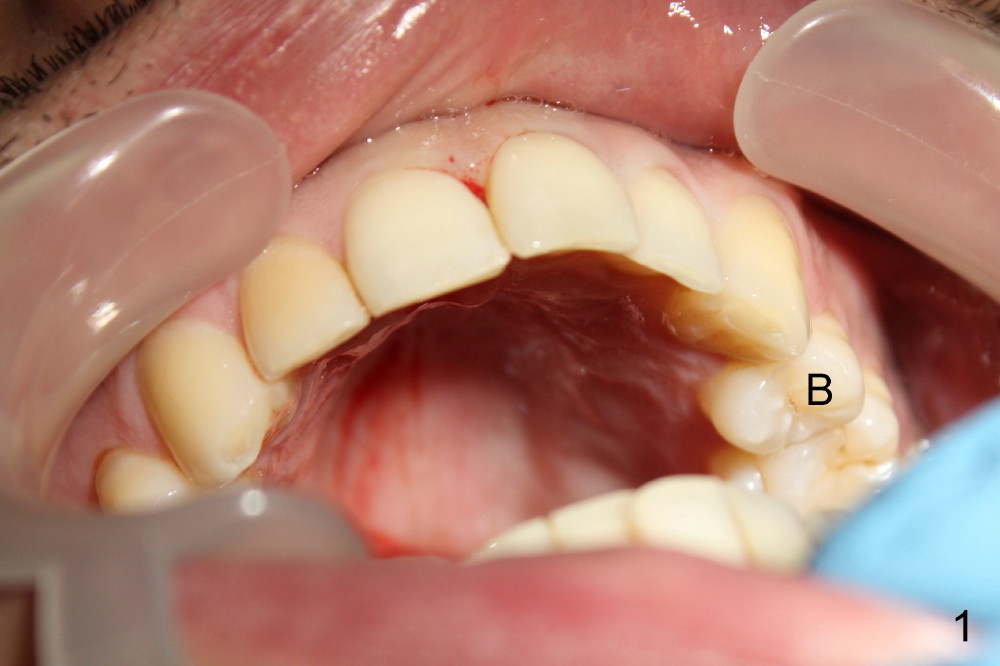

Forty-year-old man had ortho with extraction in his teens (Fig.1,2: B: bicuspid). Without wearing retainers, relapse occurs, particularly in the lower anterior. The lower left central incisor shifts labially with gingival recession (Fig.2,3). The attached gingiva is narrow for this incisor as compared to that of the neighboring tooth (Fig.4 between arrowheads). Although there is abundance of calculus, bone loss is mild to moderate (Fig.5-7). Scaling and root planing was finished today with schedule of perio maintenance every 3 months.

Both arches are narrow (Fig.1,2). Will be there space to move the lower left central lingually? Once the tooth is in normal position, gingival graft is performed to correct recession.